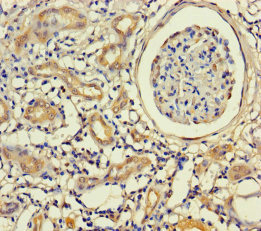

ApplicationELISA, IHC; Recommended dilution: IHC:1:20-1:200